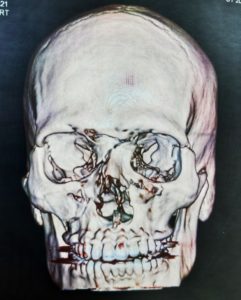

- Fraturas dos maxilares e órbita;

- Lesões craniofaciais (crânio, base do crânio e esqueleto facial);

O diagnóstico é feito pelo exame físico dos ferimentos e, nos casos de suspeita de fratura, deve se associar radiografias e tomografias computadorizadas. Esse avaliação poderá ser feita no hospital (se o paciente estiver internado) ou no consultório odontológico. O primeiro passo no tratamento é garantir a vida do paciente. O profissional deve garantir que o paciente esteja respirando bem e sem lesões graves que podem levar a morte rapidamente (como hemorragias severas, obstrução de vias aéreas e lesões de órgãos vitais)

A maioria dos ferimentos simples na pele pode ser tratada com anestesia local, limpeza da lesão e sutura. As fraturas da face e lesões complexas são tratadas sob anestesia geral. Os ossos quebrados são restaurados utilizando-se, geralmente, mini-placas e parafusos de titânio (que são biocompatíveis e não sofrem rejeição) que facilitam a recuperação e cicatrização óssea e dos tecidos